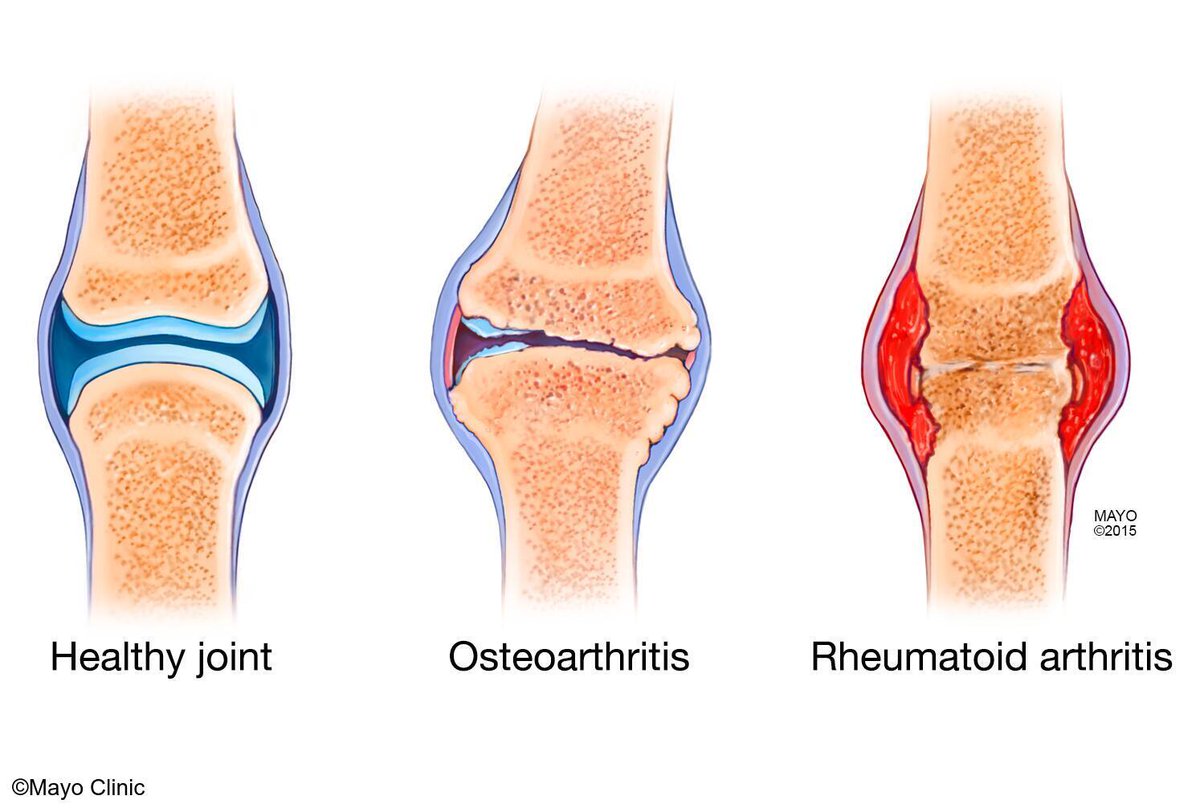

Optimize your exam of joints: 1. Tenderness along the joint line (use enough pressure to blanche the nail bed) 2. Swelling - often a sign of synovitis (different than effusion) 3. Effusion (use #POCUS) 4. Pain with range of motion Venk Bellamkonda, MD podcasts.apple.com/us/podcast/cha…

Synovitis on ultrasound is diagnosed using GreyScale findings Operator grades as follows: 0 - none 1 - mild 2 - moderate 3 - severe Venk Bellamkonda, MD podcasts.apple.com/us/podcast/cha…

Bywaters lesions are tiny microvascular infarcts that appear as small discolorations at fingertips - seen with vasculitis / rheumatoid arthritis Examples from Dr. Luciano Schiazza's website: lucianoschiazza.it/documenti/bywa… Venk Bellamkonda, MD podcasts.apple.com/us/podcast/cha…

Rheumatoid arthritis has numerous extraarticular manifestations including scleritis. scleritis is an urgent condition - watch for - severe pain - pain without relief from properacaine - pain with movements Venk Bellamkonda, MD #EyeTwitter podcasts.apple.com/us/podcast/cha…

The more RA related MSK deformities your patient has, the greater chance they will have atlantoaxial instability - be thoughtful when intubating these patients. Venk Bellamkonda, MD podcasts.apple.com/us/podcast/cha…